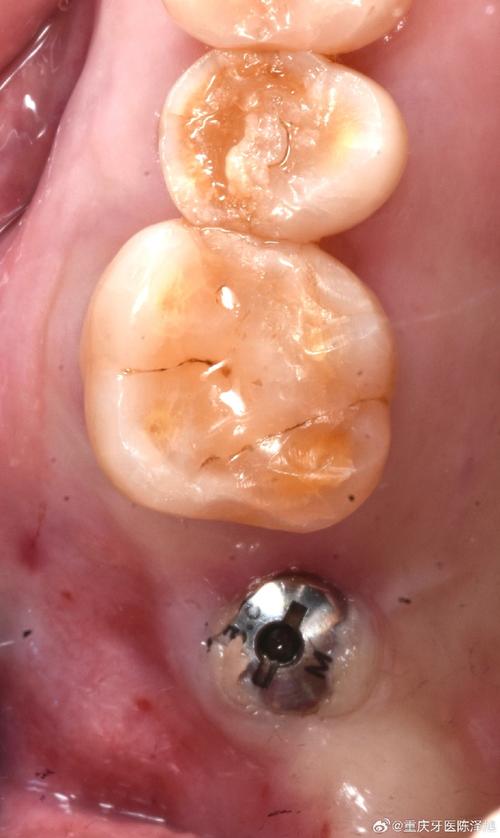

完全愈合期(1-3个月):组织重塑期

瘢痕组织逐渐成熟软化,切口形态稳定,与周围组织无明显差异,软组织愈合基本完成,种植体与牙槽骨达到良好的骨结合,可进行修复牙冠的佩戴,但需注意,即使切口完全愈合,口腔卫生仍需长期维护,使用牙线、冲牙器清洁种植体周围,防止种植体周围炎的发生,影响种植牙的长期使用寿命。